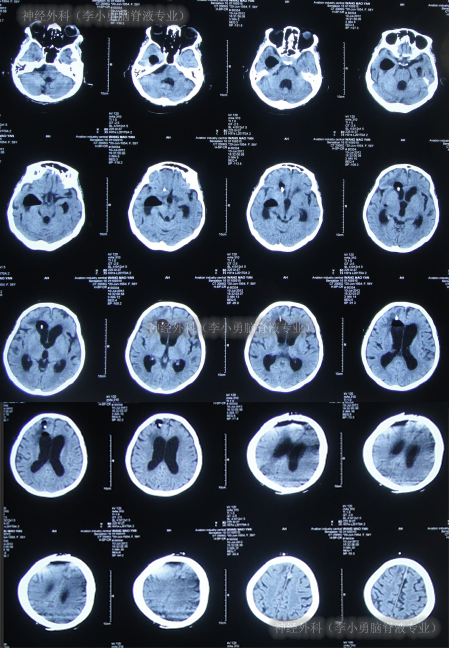

第2家医院出院1月余即2012年2月7日,夜里起夜突然又重复发作以前的症状(恶心呕吐、头昏),且比前2次发作严重,2012年2月8日住入第3家医院:呼和浩特市某三甲医院的神经外科治疗,入院查头颅CT(图-2)和MRI(图-3);脊髓核磁(图-4);肺部CT(图-5)及多次腰椎穿刺脑脊液化验检查(糖低、蛋白高),诊断为:结核性脑膜炎,脑积水。

图-2:2012年2月9日头颅CT